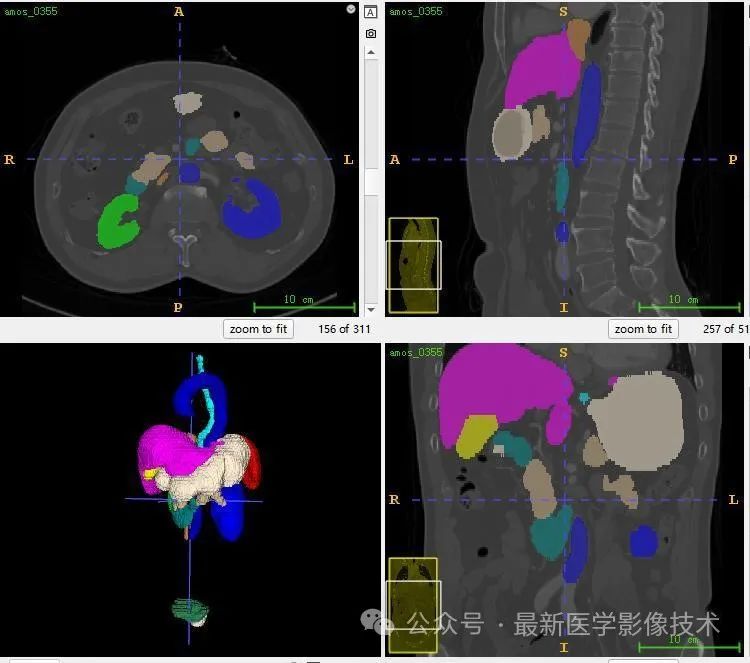

AMOS2022数据集示例说明,提供了 500 例 CT 和 100 例MRI 以及 15 个腹部器官的体素级别注释, 包括脾脏、右肾、左肾、胆囊、食道、肝脏、胃、主动脉、下腹部腔静脉、胰腺、右肾上腺、左肾上腺、十二指肠、膀胱、前列腺/子宫。请注意,某些数据点由于生理移除或由于未扫描身体部位而丢失了某些器官。

共500张CT和MRI,标注了15个器官(脾、右肾、左肾、胆囊、食道、肝、胃、主动脉、下腔静脉、胰腺、右肾上腺、左肾上腺、十二指肠、膀胱、前列腺) /子宫)呈现。请注意,某些数据点由于生理移除或由于未扫描身体部位而丢失了某些器官。

13、测试集分割结果